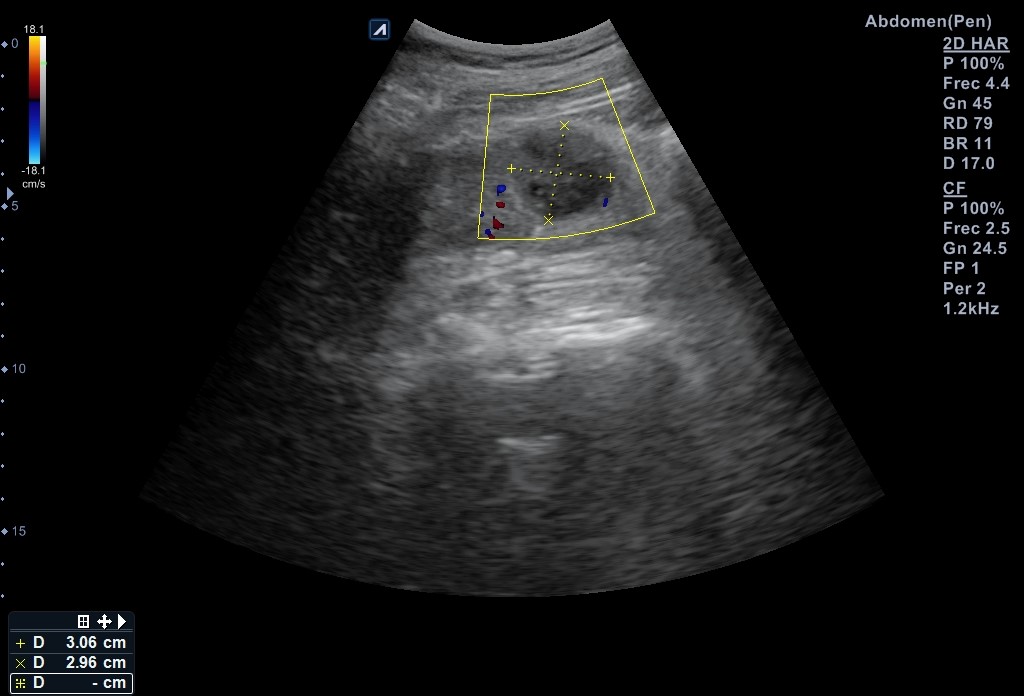

Ecografía vía urinaria: se evidencia una lesión en el tercio inferior de riñón izquierdo de aspecto quístico multiseptada, con polo sólido compatible con quiste Bosniak 3 de 30 x 29 mm que no capta Doppler, compatible en este contexto con absceso renal o neoformación renal. No otras alteraciones en resto del tracto urinario.